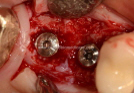

Clinical Cases

• Case1

• Case2

• Case3

• Case4

• Case5

• Case6

• Case7

• Case8

• Case9

• Case10